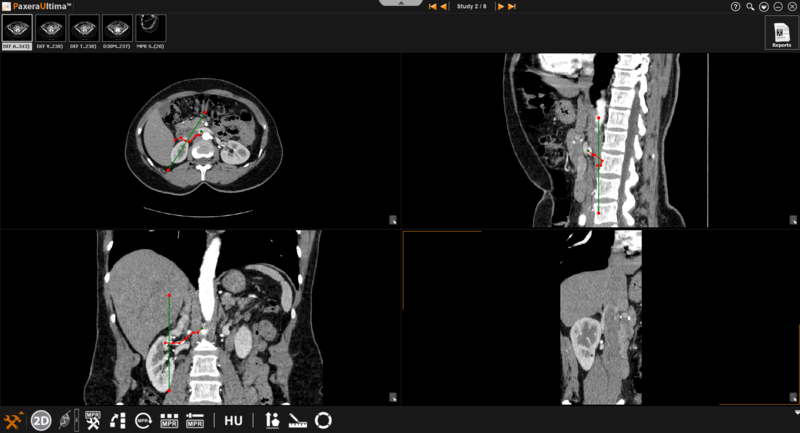

The cross curved mode is similar to the curved mode as the user is able to create a curvature view by clicking on a number of points. However, the curved line that is drawn becomes the "moving plane" and a separate line will appear as a fixed reference plane. The reference plane can be dragged along the traced curvature.

» Reference plane– indicated by the green line (see below). This plane can be moved by clicking and dragging it along the curve (shown in red). The size of the reference plane can also be adjusted by clicking on the either of the red points located at the end points of the green line and dragging it inwards (to decrease size) and outwards (to increase size)

» Moving plane– indicated by the red line. This plane can be created and adjusted as explained above for curved mode.